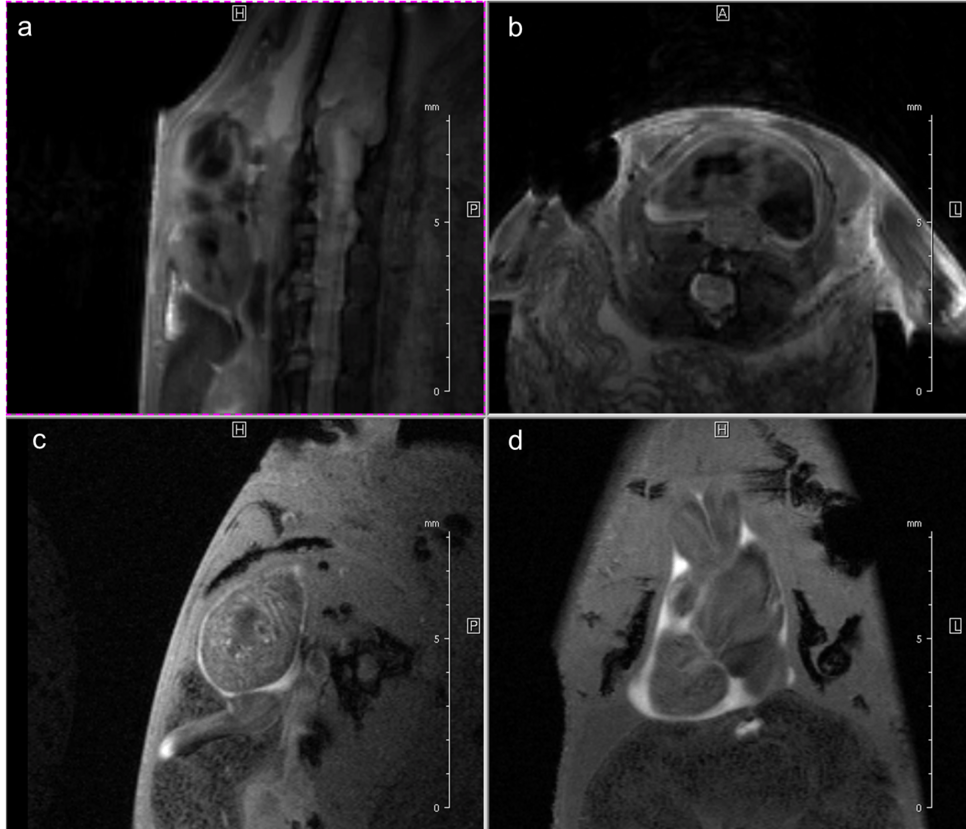

This is also due to the fact, that we use retrospective gating technique: Cardiac and respiratory cycles are detected by a navigator signal, and therefore no triggering hardware is required. The so-called “self-gating” IntragateTM Tool (Bruker BioSpin, Ettlingen, Germany) provides a steady state condition which avoids the flashing effects common to conventional ECG triggering and respiratory gating. Especially for our newt the renouncement of electrodes fixated on the tiny legs is much more comfortable for animal and investigator. The self-gating method of Intragate additionally uses intrinsically a kind of segmentation – several echoes during one heart cycle are utilized for the same image – significantly reducing the measurement time for the same SNR compared with the classical methods triggered by the ECG-signal (Fig. 3).

Fig. 3: Newt heart MRI. In the upper panel two localizer scans (RARE method (rapid acquisition with relaxation enhancement) with a repetition time of 2500 ms, echo time of 36.7 ms, slice thickness/interslice distance: 0.50/0.50 mm, field of view 2.50x2.50 cm2 and a matrix of 256/256 (a)) are shown: two 2-chamber views (a,b). In the lower panel an image of the ventricle in axial (c) and coronal (d) orientation is presented. We imaged the animal with an Intragate Flash (Fast Low Angle Shot) sequence: repetition time: 5.6 ms; echo time: 2.9 ms; oversampling: 150 (c) or 300 (d); flip angle: 10 deg; slice thickness/interslice distance: 0.3/0.3 mm; FOV: 15x15 mm and matrix: 256/256 (c) or 128/128 (d) using the 72 mm volume transmit-only room temperature and the cryogenic 4 element 1H array receive-only coil.